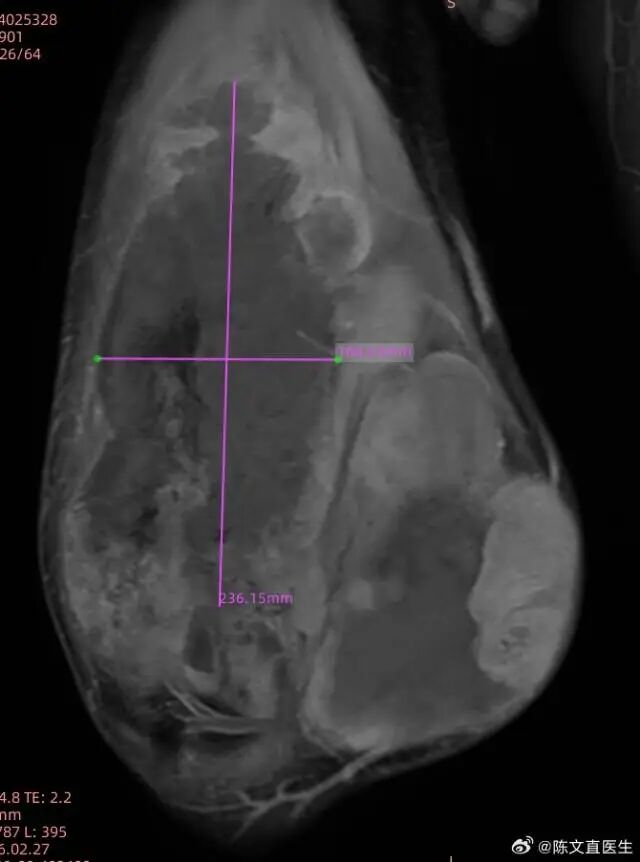

2025 年-2026 年,病情急转直下,复查显示肿瘤已疯长至 28.8 cm×15.1 cm×15.7 cm,巨大的病灶压迫周围组织,疼痛、肿胀接踵而来,当地医生建议截肢治疗。对患者而言,截肢不仅是身体创伤,更是无法接受的生活变故,他毅然拒绝,慕名来到海扶医院,寻求无创保肢的希望。

2026 年 2 月,高难度无创消融手术正式开展。面对 20 多厘米的巨大肿瘤,手术团队历时 278 分钟,成功将肿瘤组织大范围消融,术后造影可见病灶内大片无灌注坏死区,效果一目了然。

2026 年 2 月,高难度无创消融手术正式开展。面对 20 多厘米的巨大肿瘤,手术团队历时 278 分钟,成功将肿瘤组织大范围消融,术后造影可见病灶内大片无灌注坏死区。